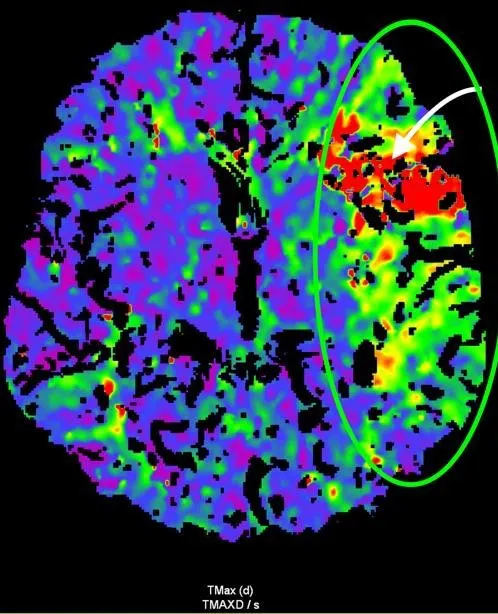

Рисунок 3. МСКТ-перфузійні зображення пацієнта Д.

Представлені карти МСКТ-перфузійних зображень демонструють зони дуже низької перфузії при CBV (a) та CBF (b), що відповідають ядру інфаркту (біла стрілка), та велику зону, що відповідаї пенумбрі (зелений овал) при TMax-map (c).

Відповідно до результатів нейровізуалізації та візуалізації церебральних артерій у пацієнта Д. був діагностований ішемічний інсульт, що обумовлений оклюзією великої мозкової артерії (лівої внутрішньої сонної артерії [ВСА] та лівої середньої мозкової артерії [СМА]). Згідно з результатами автоматичного обчислення, на момент дослідження об’єм ядра інфаркту у пацієнта Д. склав 24,6 см3, а об’єм зони пенумбри – 47,9 см3. Отже, об’єм зони пенумбри становив 194,7% об’єму ядра (співвідношення пенумбри та інфаркта майже 2:1). Зважаючи на це, ситуація була обговорена з лікарем-нейрохірургом С. В. Конотопчиком і о 14:45 пацієнт бригадою НМД «Оберіг» був доправлений у ДУ «НПЦ Ендоваскулярної нейрорентгенохірургії НАМН України» та спрямований одразу до операційної.